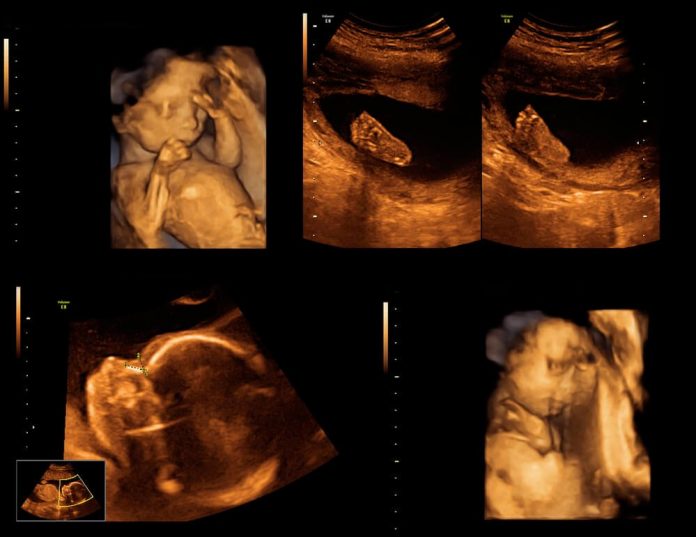

Üç-dört boyutlu ultrasonografi

Genellikle fetusun yüzünün ve diğer organlarının renklendirilmiş şekilde görüntülenmesini sağlayan, renkli fotoğrafa benzeyen, bilimsel kullanıma yaygın olarak geçmemiş, biraz da estetik ve ticari amaçla kullanılan yöntemdir. Gereksiz yere birden fazla yapılmasının yararı veya zararı henüz bilinmemektedir.